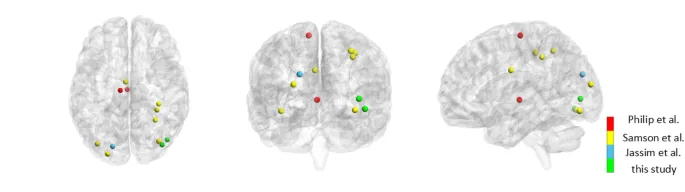

Предыдущие систематические обзоры по визуализации мозга во время перцептивных задач при РАС были сосредоточены на общем зрительном восприятии, охватывая широкий спектр парадигм зрительной обработки. Настоящий мета-анализ aims изучить механизмы мозга, специфически лежащие в основе локальной и глобальной зрительной обработки при РАС, посредством как межгруппового, так и внутригруппового мета-анализа данных активации мозга. Поэтому мы исключили несколько задач, которые были включены в предыдущие мета-анализы, такие как ментальное вращение, теория сознания и визуально направленные саккады (Philip et al., 2012; Jassim et al., 2021; Samson et al., 2012).